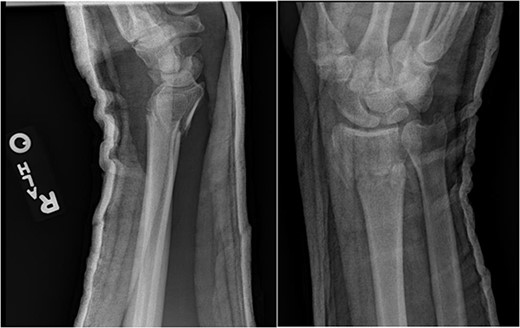

An unhelmeted 59-year-old male presented to the trauma bay at our institution after being involved in a motorcycle accident. This polytraumatized patient had been intubated prior to arrival and evaluation revealed numerous orthopedic injuries, including a right dorsal lunate dislocation (Fig. 1). Other injuries included a left distal femur fracture, left superior and inferior rami fractures, left APC II pelvic ring fracture, left closed tibia/fibula fractures, a Type III open right tibial shaft fracture, a right anterior column acetabulum fracture, and a Type I open right distal radius fracture. Traumatic subarachnoid hemorrhage to the bilateral frontal lobes, a unilateral occipital condyle fracture, a C1 fracture posterior arch fracture, a craniocervical dislocation, and numerous rib fractures were also noted. In addition to splinting all other peripheral injuries, the right distal radius fracture and lunate dislocation were closed reduced using a sugartong splint, with the wrist positioned in slight extension (Fig. 2).

Anteroposterior (AP) and lateral views demonstrating the right distal radius and perilunate dislocation after closed reduction in the trauma bay.